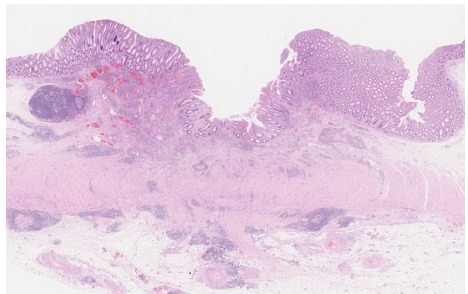

标本经福尔马林固定后每 3-5mm 组织切片。组织学检查显示明显的炎性淋巴细胞、浆细胞浸润和黏膜下层和固有肌层之间纤维化(图 6 和图 7)。解剖瘢痕处及淋巴结均没有发现癌细胞。

图 6 炎性淋巴细胞、浆细胞浸润,黏膜下层和固有肌层之间纤维化明显,表面覆盖退化的粘膜层。